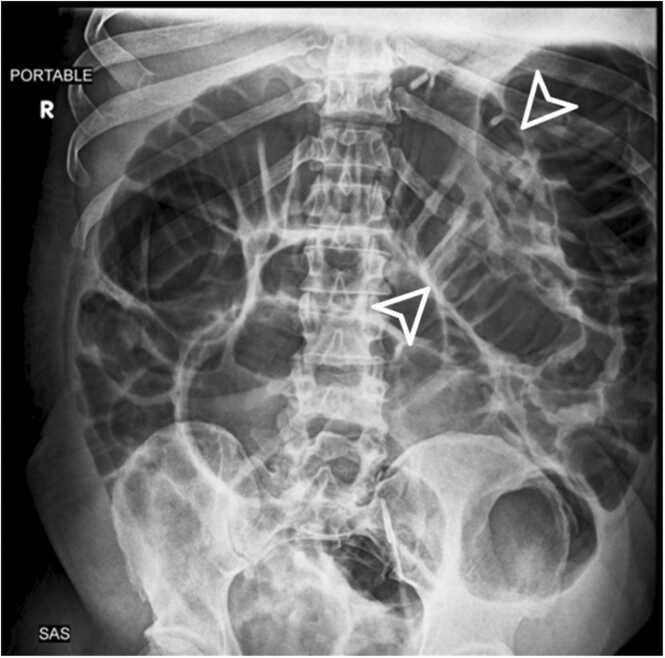

Abstract Image